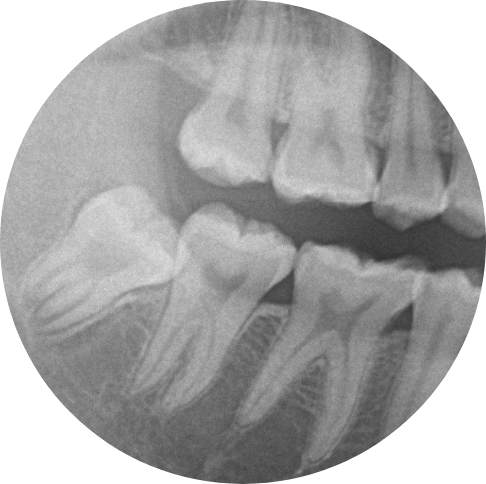

奥歯の歯と歯の間の比較的深い虫歯

1,必要に応じて麻酔を行い十分麻酔が効いた後虫歯を専用のドリルで削って除去していきます。

除去に使用する切削器具はいろいろあり、歯の状態によって都度切削器具を変えて虫歯をとっていきます。

途中痛みが出たりするようであれ麻酔を追加で入れたりしていきます。

なるべく虫歯だけを取り除き最小限の切削で処置していくのが理想ですが取り残さないのが一番大事なことになります

2,特別な神経を保護するお薬を暫間的に入れ込みます。

これにはいろいろ種類があり歯の組成と似たカルシウムを内包した材料が使用されることが多いです。

また最近ではより効果が高い材料も開発されていますが、当院では昔からある信頼性が高い材料を使用しています。

3,一定期間そのまま様子をみて各種症状が出ないようであれば型をとります。

経過観察する期間としては歯の切削状態、Drの考え方、最終的な埋める材質、患者の希望などの要素により一概にどれくらい経過を見ていくかは決まっておりません。

ただこの状態で来院が途絶えると、より深刻な状態になることがるため、必ず最終的なものが入るまでは来院していくことをお勧めしております。

4,作ってきた詰め物を調整後くっつけていきます。

作ってきたものを付けていくときに材質によっては、調整後にくっつけるパターンとくっつけた後に調整するパターンがあります、主に前者は金属を使用した詰め物ときによく見られます。

逆にセラミックを使用した詰め物の時には後者のパターンが多いです。

どちらの処理にしても最終的には綺麗になるので問題はありません。